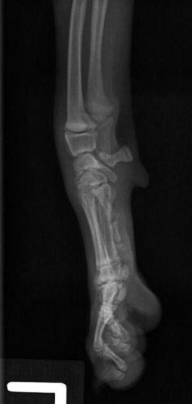

what radiograph view of the carpal joint is shown?

lateral view

what radiograph view of hte carpal joint is shown?

lateral view with carpal joint flexed at 90 degrees